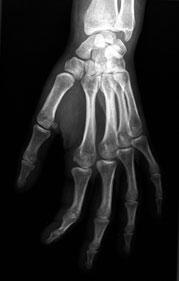

L'ostéo-arthrite est une dégénération du cartilage des articulations. Elle affecte principalement les articulations supportant le poids et est plus fréquente chez les personnes âgées. L'obésité, le stress mécanique et les mouvements répétitifs ainsi que des traumatismes importants comme des blessures provoquées par la pratique d'un sport sont des facteurs qui contribuent à son développement. L'ostéo-arthrite est responsable de douleurs dans les articulations qui limitent les déplacements et les mouvements et d'une perte de dextérité. Les symptômes de l'ostéo-arthrite apparaissent généralement à la cinquantaine et vers l'âge de 60 ans, la plupart des gens en souffrent à des degrés divers.

La médecine moderne traite l'ostéo-arthrite avec trois types de médicaments : les anangésiques comme les salicylates, les médicaments anti-inflammatoires non stéroïdiens et les médicaments anti-inflammatoires stéroïdiens. Outre qu'ils provoquent des effets secondaires, pratiquement tous ces médicaments ont des effets destructeurs sur les cartilages recouvrant les os de l'articulation. Chaque classe de médicament contribue à la destruction de l'articulation par un mécanisme différent. A l'inverse, la SAMe protège et répare les articulations en augmentant le nombre des chondrocytes, les cellules du cartilage, en stimulant la synthèse des protéoglycanes par les condrocytes articulaires et en diminuant la perte de cartilages.

Après avoir examiné 14 études consacrées au traitement de l'ostéo-arthrite, l'équipe de chercheurs a conclut dans son rapport que la SAMe semblait avoir une action aussi efficace que celle des médicaments anti-inflammatoires non stéroïdiens.